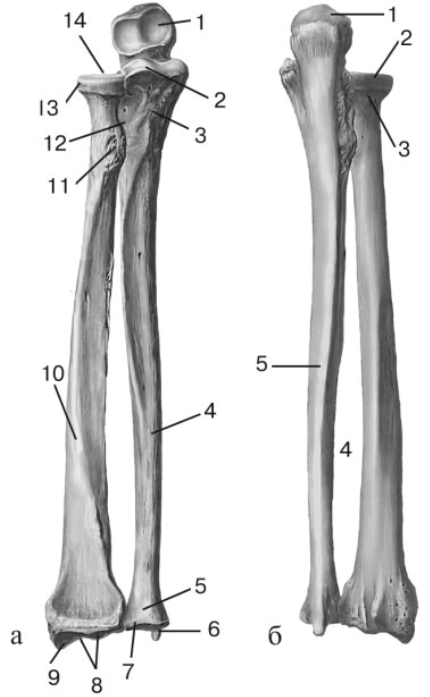

Радиоульнарный угол: строение и особенности лучевой кости